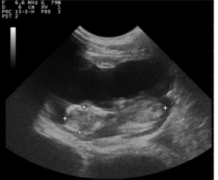

羊用B超机超声检查通过不同路径形成的是可靠的诊断工具用于妊娠早期诊断,确定胎儿数量和公母,以及GA的估算山羊怀孕。超声的最新进展软硬件技术都有产生了卓越的图像超声波在……